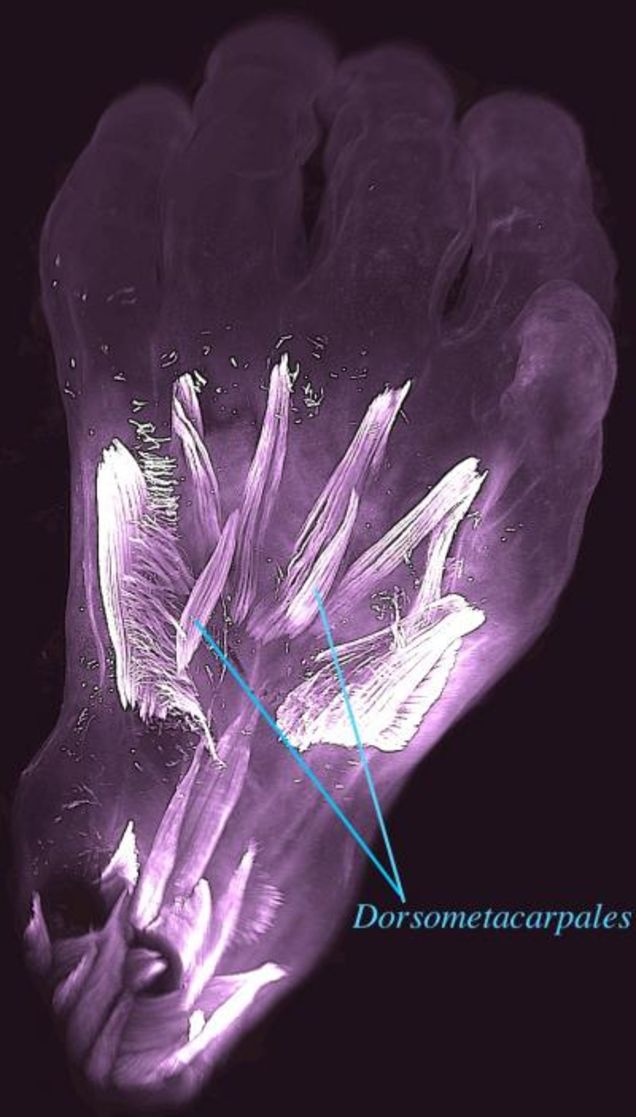

En la mano y el pie de un feto de siete semanas, por ejemplo, pudieron encontrar 30 músculos individuales. Pero para la semana 13 de gestación, un tercio de los músculos se habían desvanecido o fusionado. Un par de estos músculos atávicos, como se los conoce, se llaman dorsometacarpales. Y aunque todavía se encuentra en muchos animales con extremidades hoy en día, incluidos lagartos y salamandras, parece haber dejado de aparecer en nuestros antepasados adultos hace 250 millones de años.